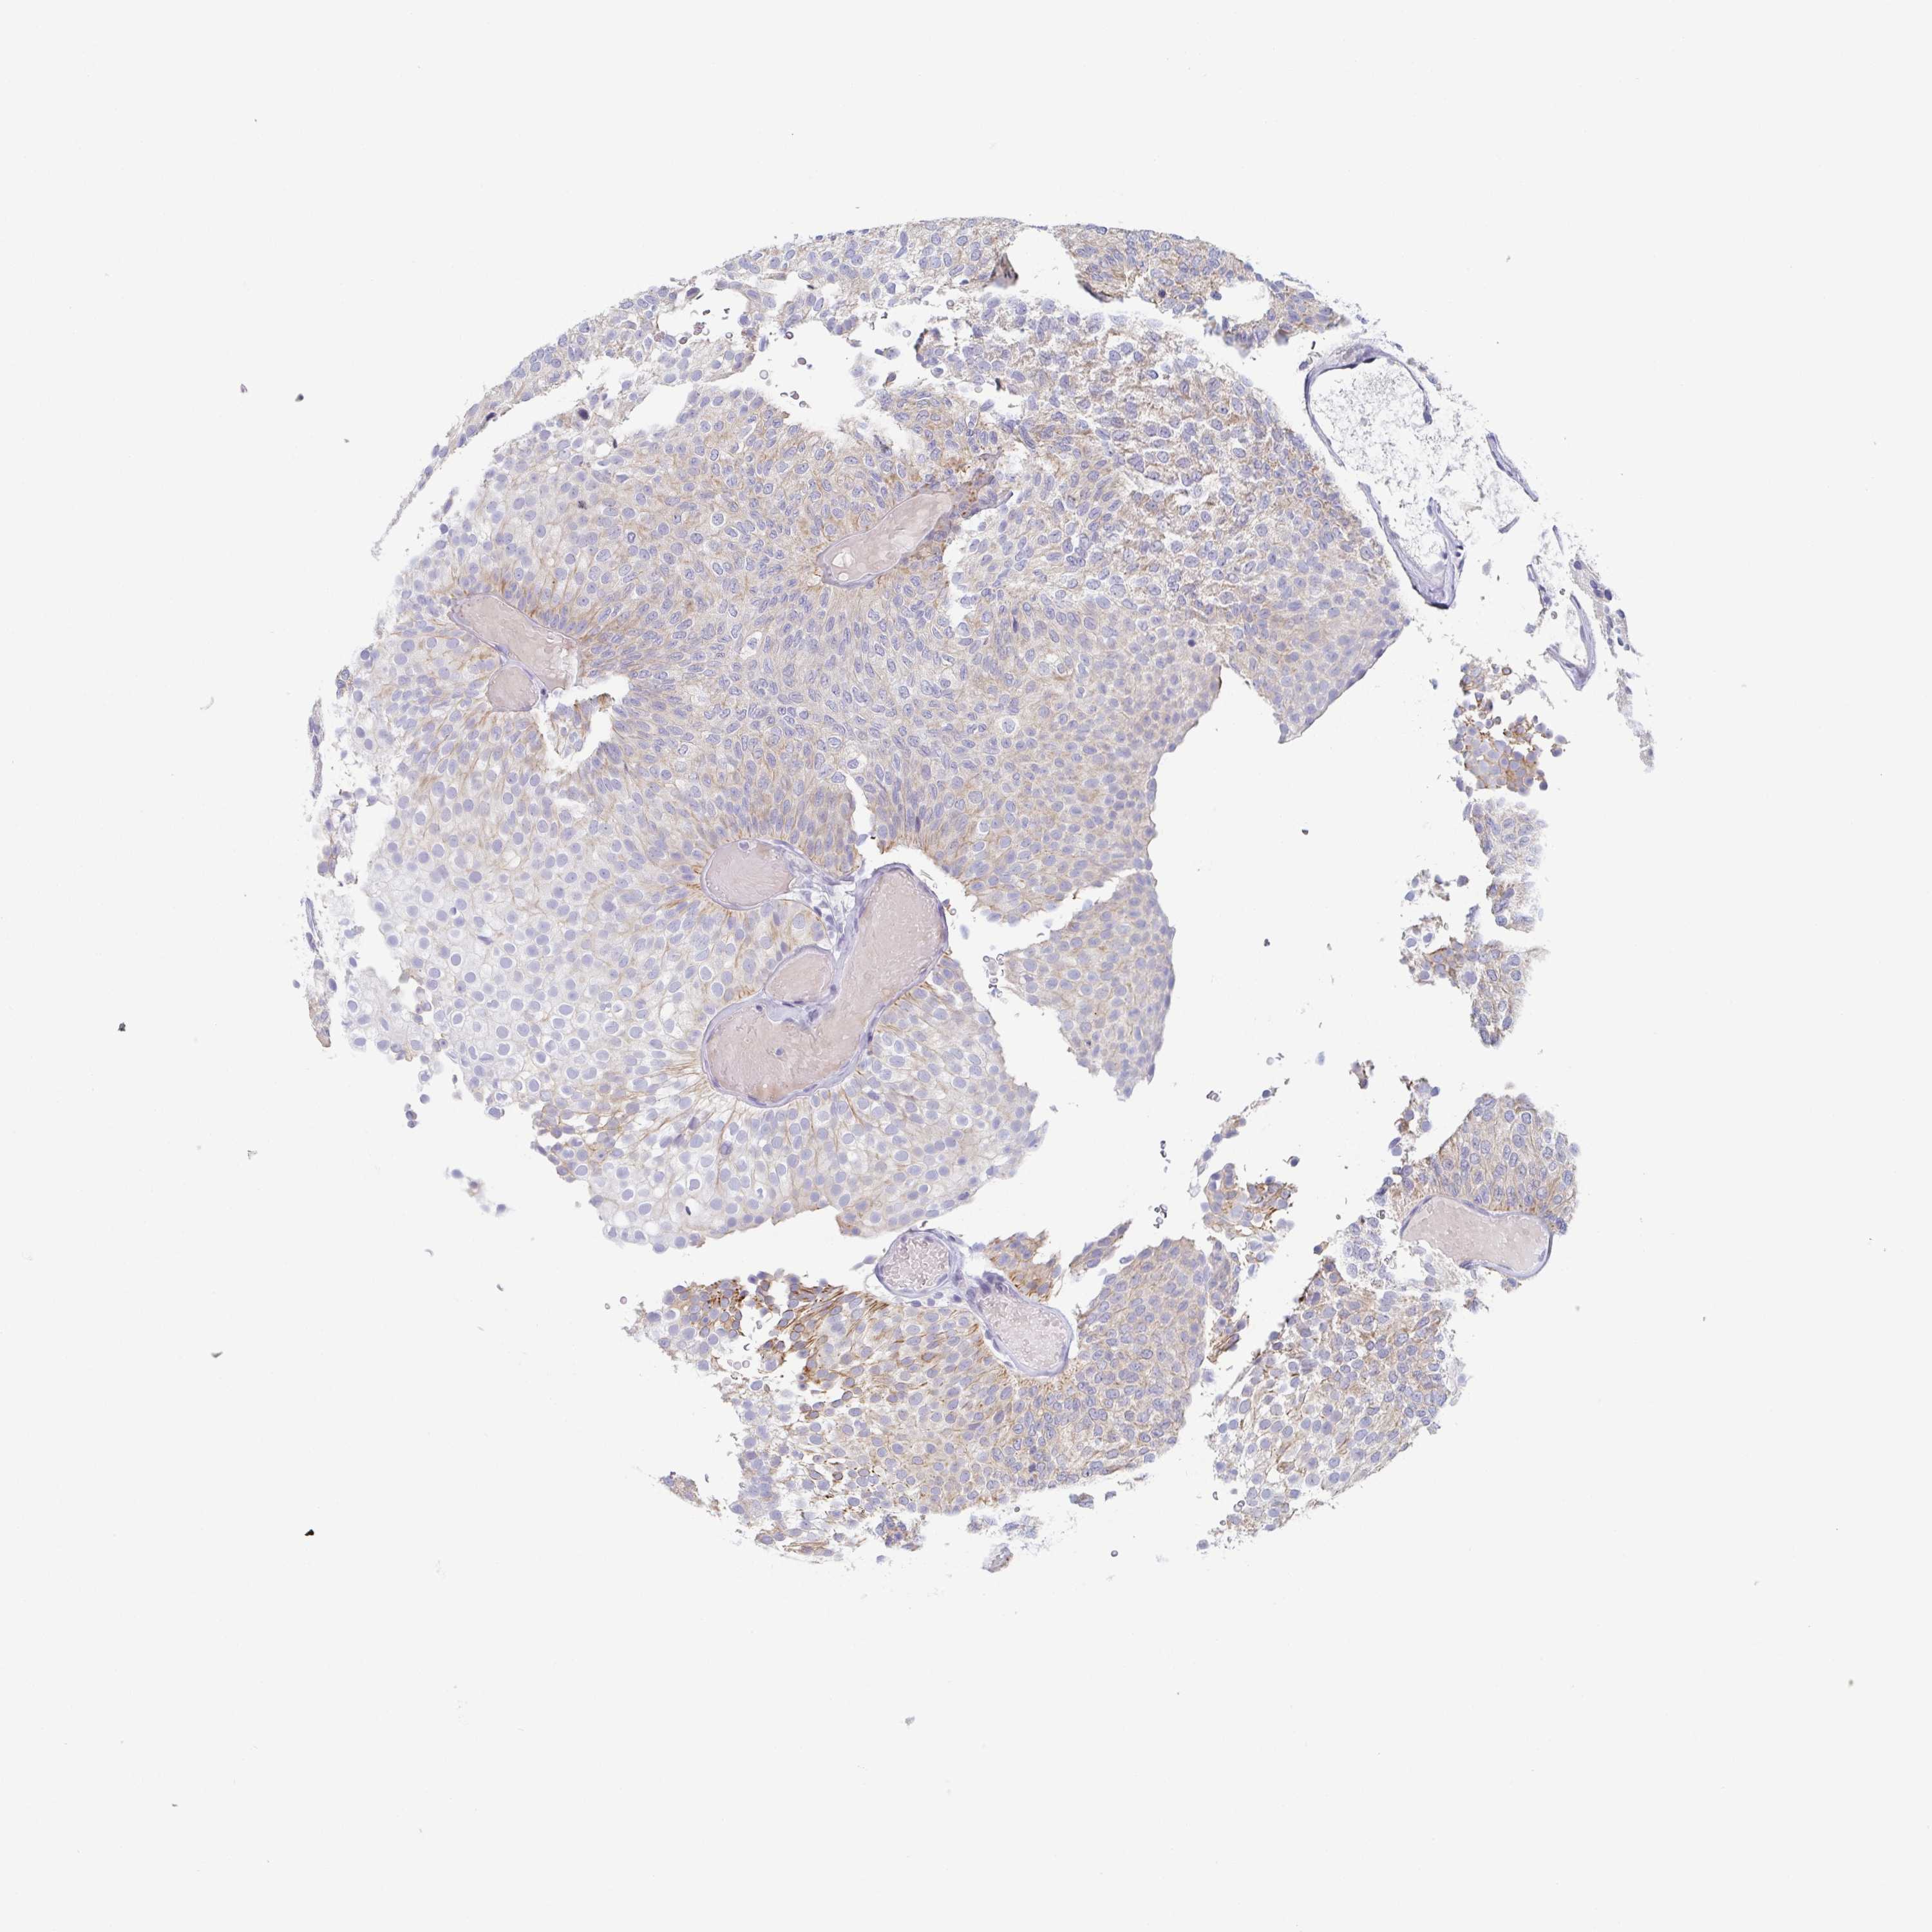

UROTHELIAL CANCER - Protein expressioni

A mouse-over function shows sample information and annotation data. Click on an image to view it in a full screen mode. Samples can be filtered based on level of antibody staining by selecting one or several of the following categories: high, medium, low and not detected. The assay and annotation is described here.

Note that samples used for immunohistochemistry by the Human Protein Atlas do not correspond to samples in the TCGA dataset.

Antibody stainingi

Antibody staining in the annotated cell types in the current human tissue is reported as not detected, low, medium, or high, based on conventional immunohistochemistry profiling in selected tissues. This score is based on the combination of the staining intensity and fraction of stained cells.

Each image is clickable and will lead to virtual microscopy that enables deeper exploration of all samples and also displays staining intensity scores, fraction scores and subcellular localization as well as patient and tissue information for each sample.

Antibody HPA053343

Staining

High

Medium

Low

Not detected

Intensity

Strong

Moderate

Weak

Negative

Quantity

>75%

75%-25%

<25%

None

Location

Nuclear

Cytoplasmic/membranous

Cytoplasmic/membranous,nuclear

Urothelial carcinoma, High grade

Urothelial carcinoma, Low grade